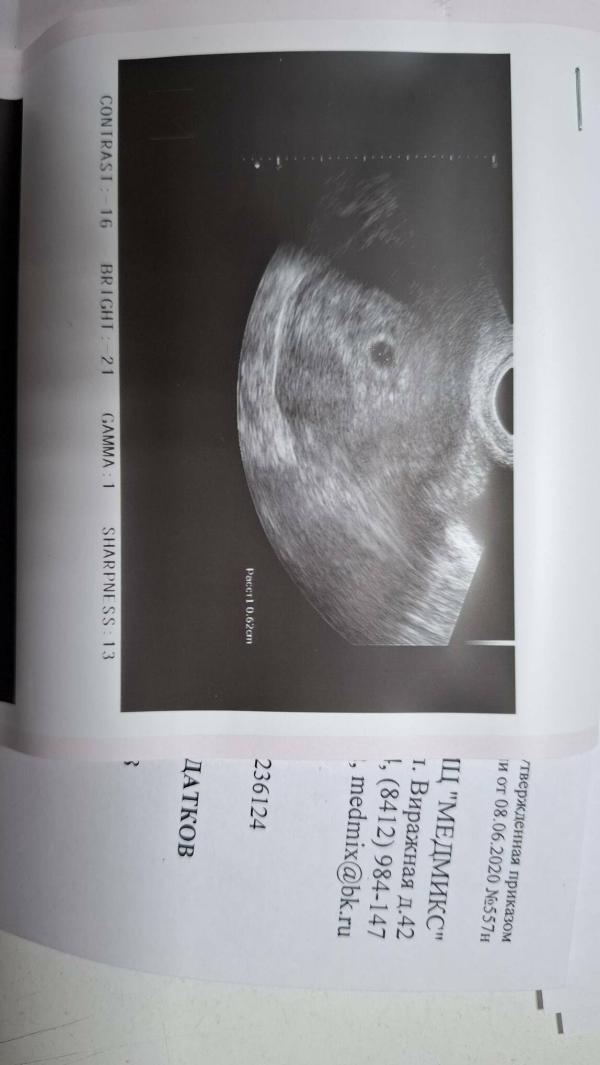

УЗИ на 4-5 неделе беременности: ПЯ 7 мм, что это значит? Видно ли желточный мешочек?

Сегодня наконец-то тоже побывала на узи, ПЯ 7 мм, 4-5 недель примерно. Правда ничего про желточный мешочек не сказали, наверное еще рано или вот маленькое пятнышко в центре оно и есть?